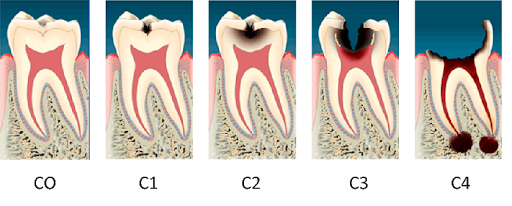

虫歯の進行

早期発見・早期治療を

虫歯は急激に進行する訳ではなく、時間をかけて進行していきます。

ごく初期段階であるC0(経過観察)を過ぎると、虫歯はどんどん悪くなっていきます。歯は一度悪くなれば元の状態に戻ることはないということをしっかり理解しておくことが大切です。

歯科医院では虫歯は進行段階によって「C0」「C1」「C2」「C3」「C4」という記号で表し、初期段階のC0の段階であれば適切な処置を行えば歯を削ることなく再石灰化によって自然治癒することも可能です。 しかしながら、それ以降のC1~C4という段階の場合は歯科医院で治療を行う必要があります。

C1 エナメル質が溶けて表面に穴があいた状態

虫歯の初期段階がC1です。この段階では虫歯を削ってレジン(プラスチック)を詰め、1回で治療を完了させることが出来ます。

C2 虫歯が象牙質にまで広がった状態

C2の段階になると、冷たいものが染みるようになります。この段階までなら歯を削る量を出来るだけ少なくすることが可能です。治療回数も1~2回程と、比較的短期間で治療が完了します。

C3 歯がかなり失われてしまった状態

C3まで進行すると、痛みなどの自覚症状はC2の時よりも多くなります。この段階以降は虫歯が神経まで達してしまっているため、一般的には神経を取り除く治療を行うことになります。

C4 歯の根だけしか残っていない状態

この段階まで虫歯が進行しまうと、残念ながら基本的には歯を残すことが出来なくなってしまいます。ただし、歯の根や周囲の骨の状況などによっては歯を残すための治療が可能な場合もありますので、まずは当院までご相談ください。

※虫歯がC4の段階まで進行すると、通常の場合、痛みはなくなります。 痛みがなくなると「歯科医院に行って治療しなくてもいいか」と考える方も少なくありませんが、これは非常に危険です。なぜなら、痛みが消えたのは虫歯が治ったからではなく、歯の神経(歯髄)が死んでしまったからです。その間にも歯は細菌によって溶かされ、腐らされています。早めに歯科医院を受診するようにしましょう。